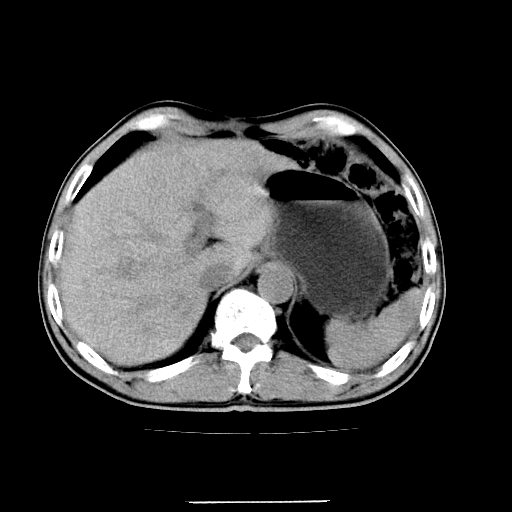

应该考虑是肠管,理由1、平扫和增强对比,形态和内部的密度有明显改变。2、增强图片可见明显气液平面。

一个形态变化大应该是肠管。

另一个上下观察不成形,强化也不符合淋巴结表现故考虑术后改变。

另外,胰腺体部密度在平扫和增强时均不太均匀,似有数个小的囊状低密度区存在。不知道增强时其他期如何?应该高度警惕为转移性病变。

胰头右侧低密度影卡考虑为肠管;胰头前部低密度影,增强环形强化,结合临床首先考虑转移灶,其次考虑淋巴结结核(中心干酪性坏死)。

如是转移灶强化多为均质强化。如是结核应见到完整的壁且壁略厚。如是转移虽壁可不完整但内壁应该不规则。所以不支持是结核或转移。敬请指正!